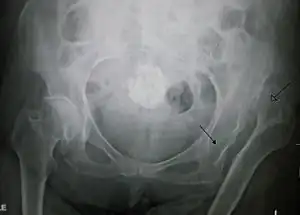

Anterior-posterior (AP) X-rays of the pelvis, AP and lateral views of the femur (knee included) are ordered for diagnosis.[13] The size of the head of the femur is then compared across both sides of the pelvis. The affected femoral head will appear larger if the dislocation is anterior, and smaller if posterior.[14] A CT scan may also be ordered to clarify the fracture pattern.

Congenital hip dislocation -

Anterior dislocation of the hip -